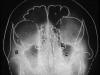

Рис. 54. Схема с электрорентгенограммы черепа в

передней полуаксиальной (подбородочной) проекции.

1—крыша глазницы; 2—скуловая кость; 3— альвеолярная бухта верхнечелюстной

пазухи;

4- пирамида височной кости;5-лобная пазуха; 6— полость носа; 7— угол нижней

челюсти; 8—1 шейный позвонок; 9—2 шейный позвонок.